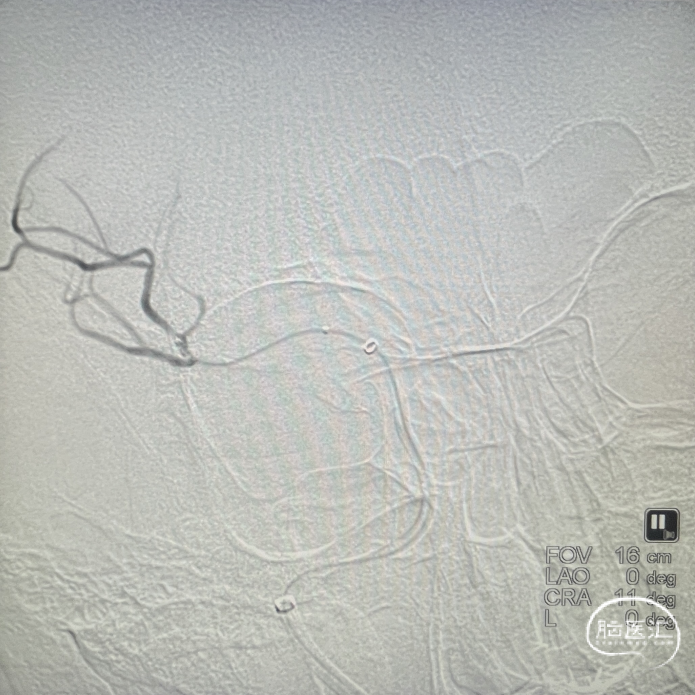

术前DSA影像:造影显示患者右侧大脑中动脉闭塞。

右侧颈内动脉造影—M1段闭塞